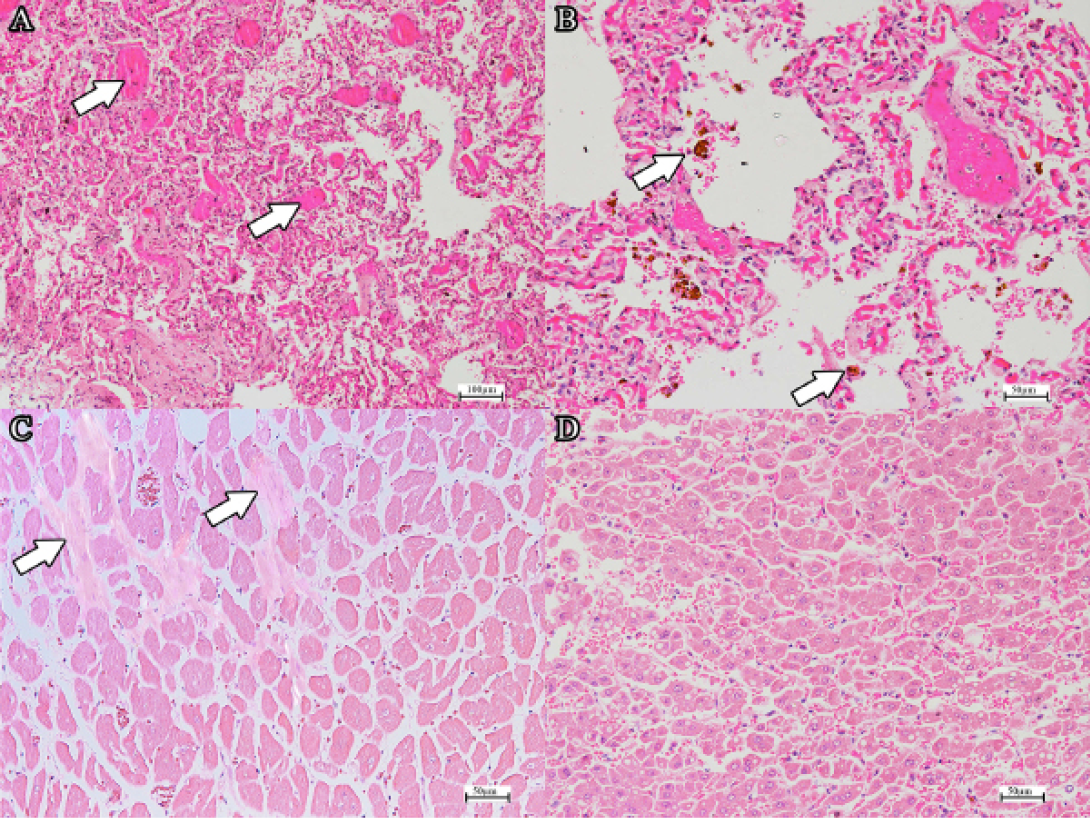

(a) DIC in the pulmonary capillaries (arrows) (H and E, bar=100µm). Note the extensive atelectasis. (b) Haemosiderin-laden alveolar macrophages (H and E, bar=50µm). (c) Mild fibrosis of the myocardium (arrow) (H and E, bar=50µm). (d) Generalised mild to moderate hepatic lipidosis (H and E, bar=50µm).